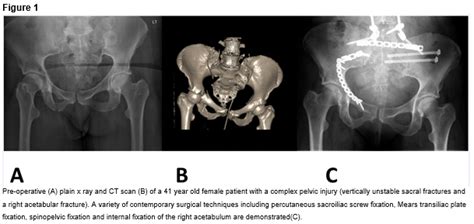

In surgeries to repair pelvic and acetabular fractures, a combination of metal screws, plates, pins and bars are used to realign the fractured and injured.

Acetabular rim fracture/os acetabuli refixation. 14 mgh series from 188 consecutive revisions by one surgeon, 122 had 10 year plus data, average 12.5 years. Because acetabular fractures damage the cartilage surface of the bone, an important goal of surgery is to restore a smooth, gliding hip surface. Acetabulum fractures are often treated with the surgical methods are used in which reconstruction plaques and fixators or screws using open anatomic reduction. Video lecture with narrations and live annotations from orthoclips.com. By cyril mauffrey 10 videos. French society for orthopaedic surgery and traumatology (sofcot). During the operation, your doctor will reconstruct the normal anatomy of the hip joint—aligning the. Related online courses on physioplus. #treatment type i and type ii try to reduced it with maneuver used for post dislocation, if failed. Post acetabular fracture surgery performed by dr. Acetabular rim fracture/os acetabuli refixation. Pelvic and acetabular (hip socket) fracture surgery is done to help patients regain normal function by realigning and stabilizing the fracture. An acetabular fracture results when a force drives the head of the femur against the acetabulum. Lecture on geriatric acetabulum fracture management. Most acetabular fractures are treated with surgery. Acetabulum and pelvis is a connection between the upper and the lower part of the body.